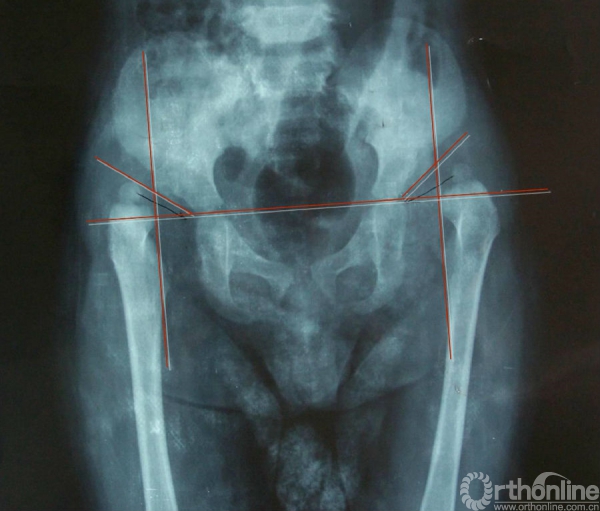

X线检查(CE角)

即中心边缘角。自股骨头旋转中心至髋臼顶的外缘画一直线,另自髋臼顶外缘作一垂线,两线所成的角即为CE角。正常时约为20°~40°,小于此度数说明头臼关系失常。15°~19°为可疑;少于15°,甚至负角,表示股骨头外移,为脱位或半脱位。

双髋关节脱位Ⅱ度